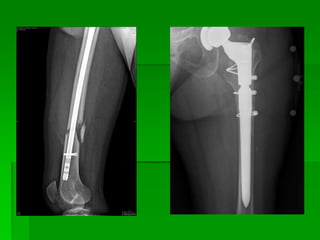

Técnica de cuello de

fémur Quirúrgica

Tamaño de película:

24x30 Longitudinal D.F.P: 1 m

Posición del paciente: El paciente se encuentra

en decúbito dorsal,

supino, el miembro en estudio extendido y rotando

internamente.

El miembro opuesto tiene que ser sacado

de la zona para evitar

suma de imágenes.

La extremidad sana, levantada, cadera en

abducción y flexión de

rodilla, la planta del pie apoya sobre la mesa.

Verificar que la pelvis no este rotada

Rayo Director: Incide

horizontalmente centrado en la

mitad del fémur, (que esta en posición lateral)

entre el trocánter mayor y el pulso femoral.